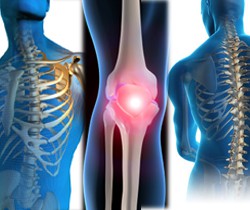

A ortopedia é a especialidade médica que cuida das doenças e deformidades dos ossos, músculos, ligamentos, articulações, enfim, elementos relacionados ao aparelho locomotor. A traumatologia é a especialidade médica que lida com o trauma do aparelho músculo-esquelético.

No Brasil as especialidades são unificadas, recebendo o nome de "Ortopedia e Traumatologia" e também a especialidade da odontologia intitulada cirurgia e traumatologia bucomaxilofacial que, por sua vez, cuida do complexo...